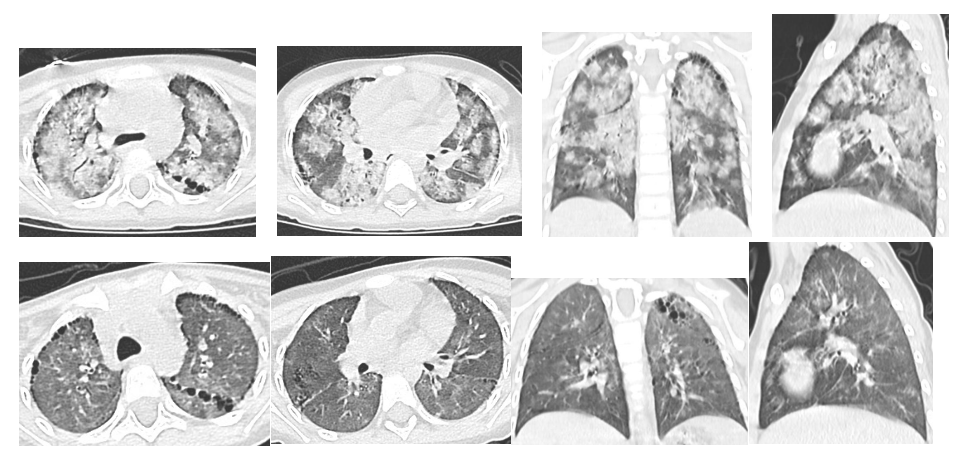

图片

复查前后CT对比  图源长沙市妇幼保健院订阅号